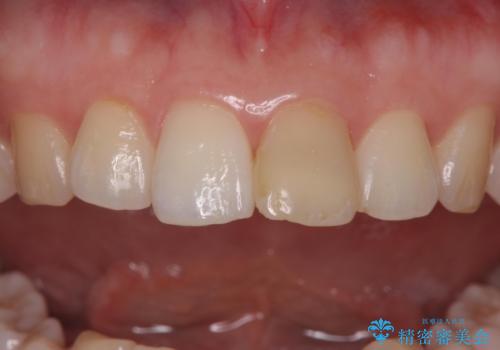

根管治療からやり直しを行った後、ジルコニアクラウンで修復することで、ガタつきと変色の両方を改善していきます。

- 左上1/再根管治療66,000円+ファイバーコア22,000円+仮歯11,000円+ジルコニアクラウン(スタンダード):121,000円 合計209,000円(税込)費用は治療当時の料金となります